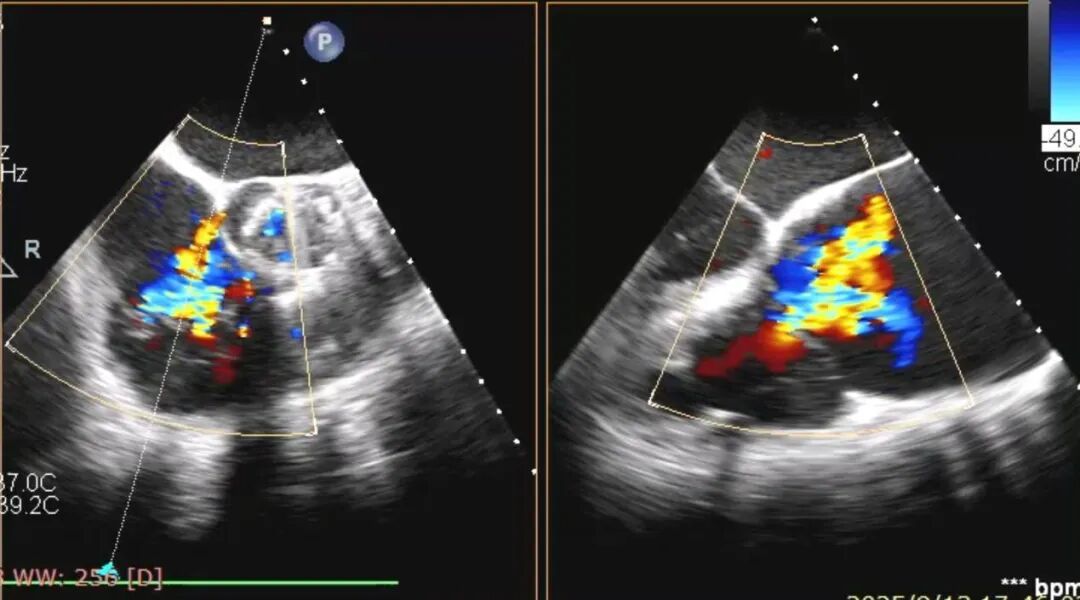

术前食道超声提示三尖瓣重度反流。

术后食道超声提示反流情况明显好转。

手术当天,术前经心脏超声及CTA检查,患者三尖瓣环扩大明显,反流位置复杂。手术团队根据影像结果精准规划,分别于后瓣环及前、后瓣环处植入两枚K-Clip夹合装置,就像在心脏的后背“门框”和前后交界各夹一枚“夹子”,增强瓣叶对合。术中,患者血流动力学稳定,手术顺利完成。术后即时评估显示,患者心脏由原来的“大漏水”变成“轻微渗水”,喘和肿也明显减轻。手术效果显著,患者症状迅速缓解。